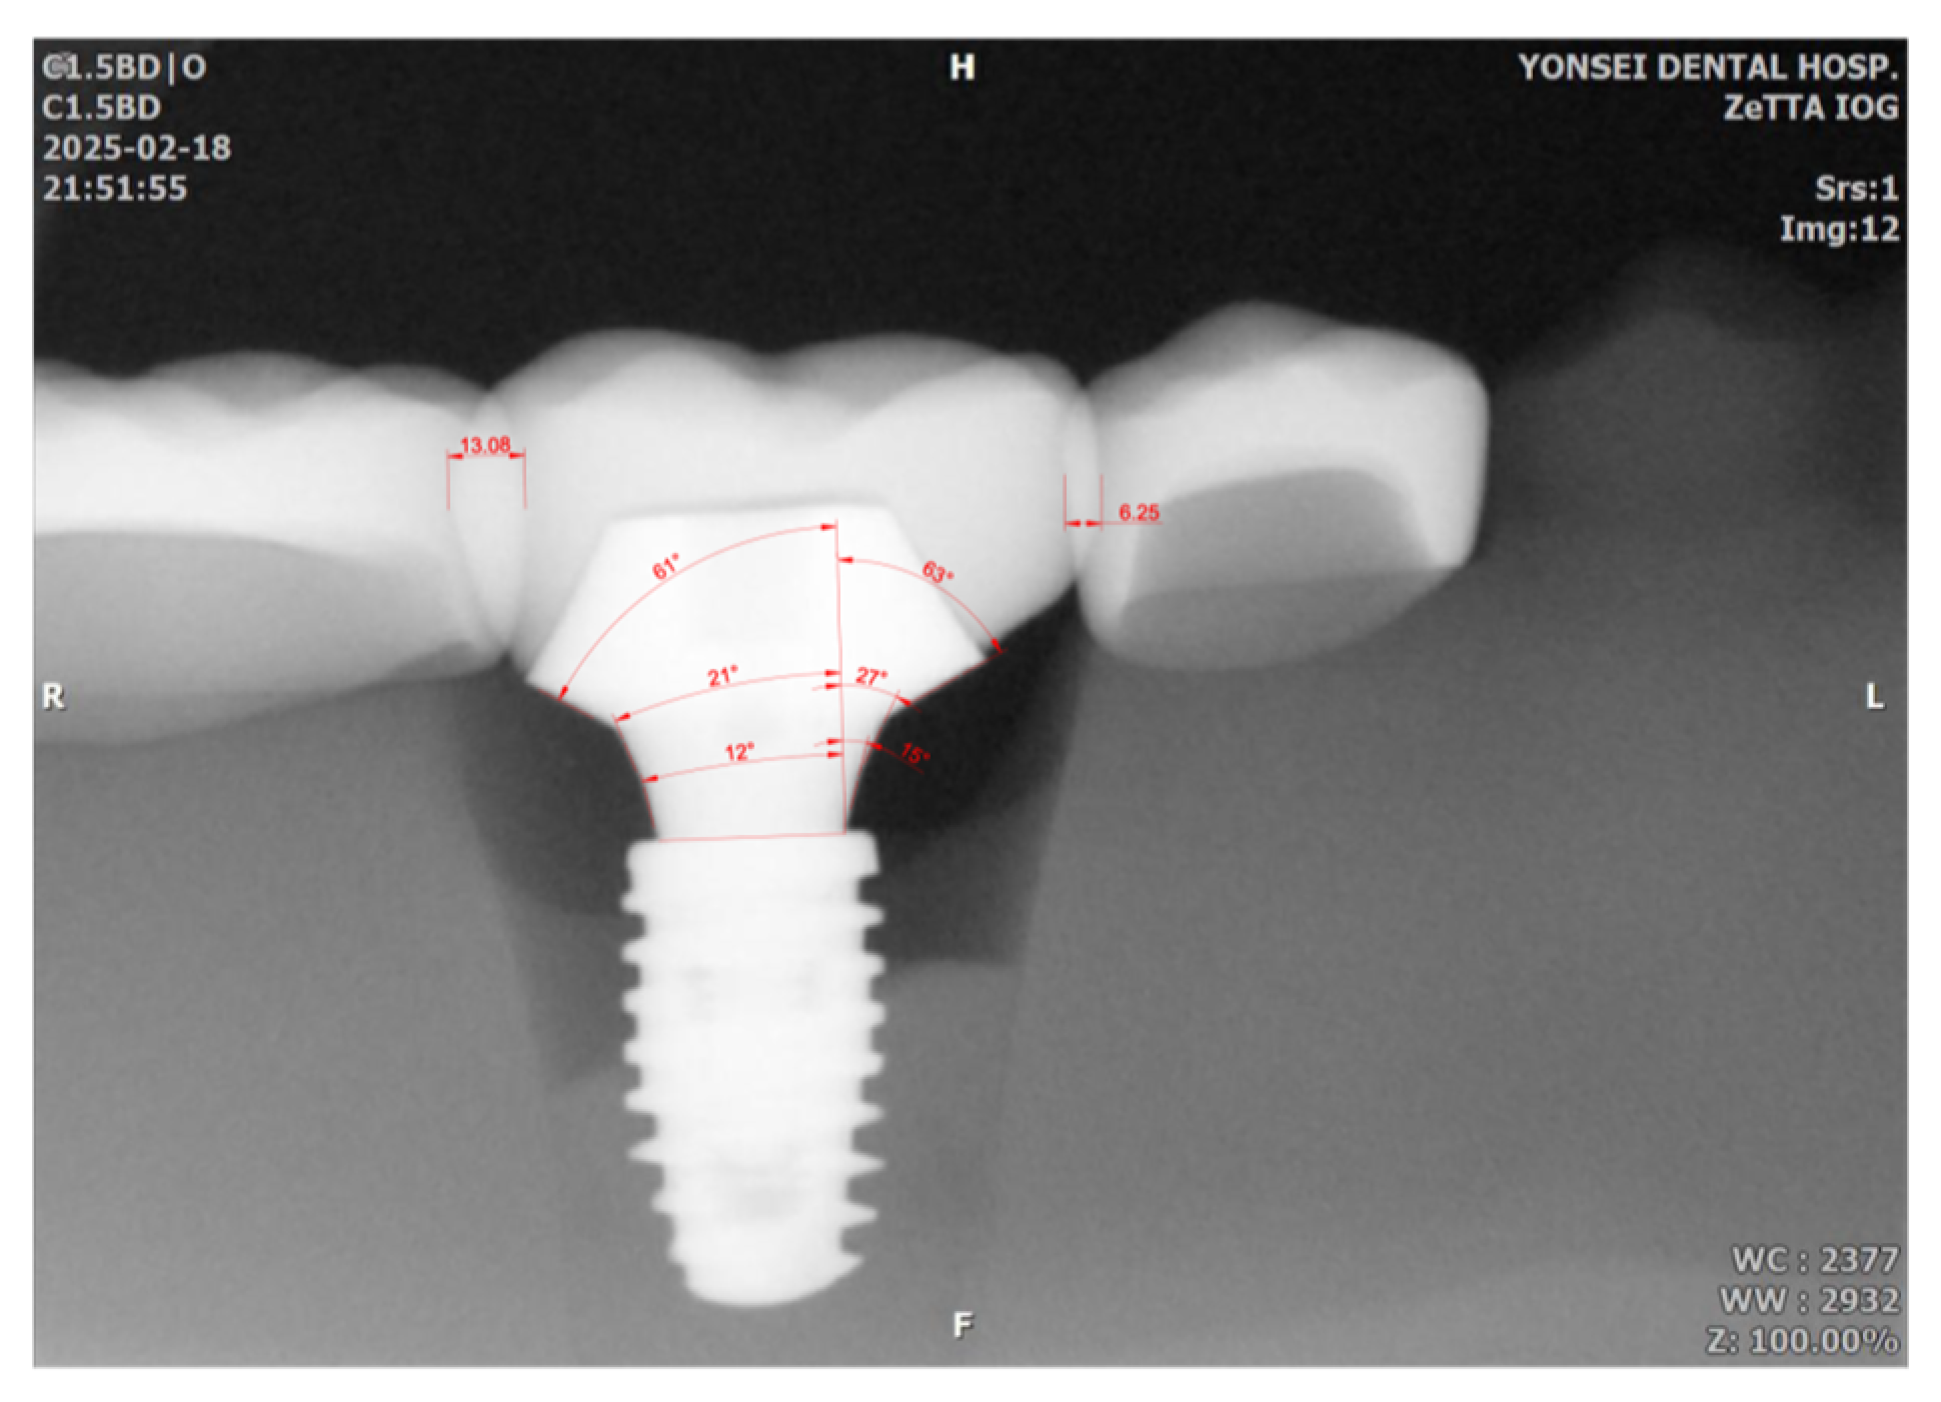

Sensor rotation also led to measurable distortion in profile angle measurements. When compared to the STL reference values (15°, 25°, 60°), the deviations ranged from −6° to +5°, with the maximum deviation (2.3°) observed in Group L15. Mean mesial deviations increased from 0.7° to 2.1°, and distal deviations from 0.8° to 2.1° across 5°, 10°, 15°, and 20° rotations (Figure 6 and Table 6).

Figure 6.

Measurements of mesial and distal profile angles and the amount of proximal overlap between adjacent restorations. Mesial and distal profile angles were measured across 3 distance ranges, resulting in 15°, 27°, 63° for the mesial aspect, and 12°, 21°, 61° for the distal aspect. The overlap values in the distal and mesial aspects were 13.08 and 6.25, respectively, in this image (the number represents units in the CAD program, not millimeters). The number was divided by the mesio-distal width of implant restoration (110.68 which is not shown in this picture) resulting in 11.8% and 5.6% for distal and mesial aspect of the implant restoration.